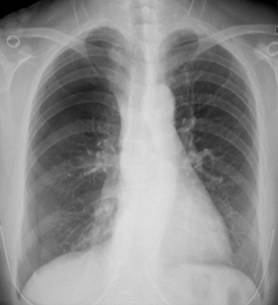

照片名称:胸腔积液